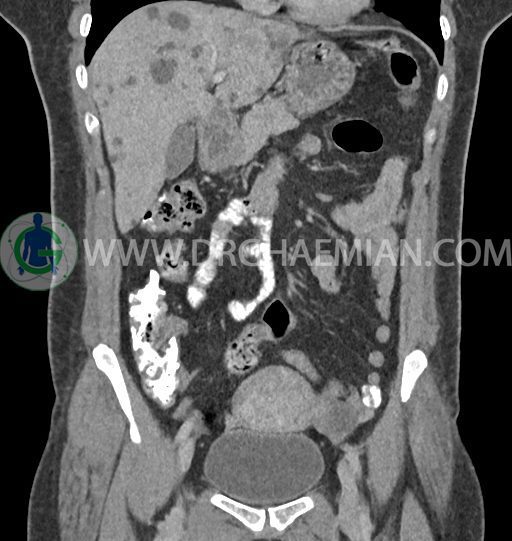

سی تی اسکن شکم و لگن با استفاده از اشعات ایکس تصاویر عرضی از ناحیه شکم و لگن ایجاد میکند. در این کیس کبد پلی کیستیک، کیست در تخمدان چپ، توده در دیواره سرویکس و اسپوندیلولایزیس دو طرفه مهره L5 دیده می شود.

در سی تی اسکن اسپیرال شکم و لگن – 5Phasic (بدون کنتراست – با کنتراست در فاز آرتریال ، پورتال و تاخیری 5 دقیقه و 10 دقیقه، مولتی دیدکتور 16 با مقاطع ظریف و بازسازی های ساژیتال و کرونال) :

-ضایعات سیستیک فراوان به قطر 5 تا 30mm پراکنده در کبد بدون جزء سالید، بدون septation و بدون اینهنسمنت پس از تزریق کنتراست مطرح کننده polycystic liver disease

-کیست ساده به قطر 31mm در تخمدان چپ

-توده هیپودنس به قطر 13mm در دیواره قدامی سرویکس نیازمند مطابقت سونولوژیک

-اسپوندیلولایزیس دو طرفه L5 همراه با آنترولیستزیس gread 1 و تغییرات DJD در L5/S1

مشهود است.